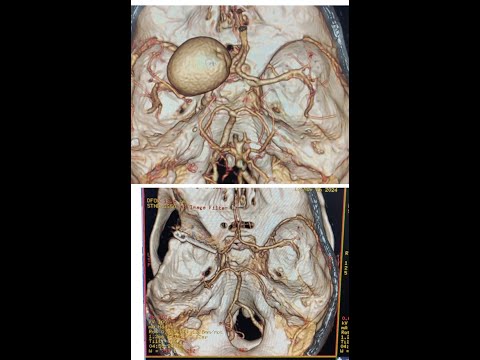

Hellow guys, Welcome to my website, and you are watching D11 D12 NEUROFIBROMA-DR LAXMIKANT BHOPLE/DR SANDEEP GORE SHREE GANGA HOSPITAL NANDED. and this vIdeo is uploaded by Dr. Laxmikant Bhople NeuroCare at 2024-07-24T04:56:42-07:00. We are pramote this video only for entertainment and educational perpose only. So, I hop you like our website.